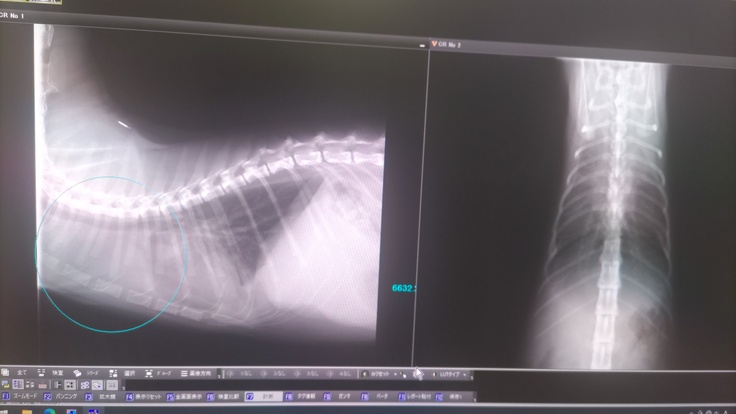

肝臓の腫瘍 約7cm×4cmの巨大腫瘍 写真中央の十字点線で示しているのが腫瘍です

胸部 約3cm×2cmの腫瘍 こちらも見づらいですが、薄く十字点線で示しているのが腫瘍です

青で囲っていうのが胸水となります。

レントゲンで撮影したところ、ステロイドが良く効き、腫瘍がほぼ小さくなったことで、胸水もほぼ無くなりました。

↓治療のおかげで腫瘍がほとんどなくなりました。

左の写真が現在の胸の腫瘍(ほぼ無し)、

右の写真が7/15の時の腫瘍(3cm×2cm)

左の写真が現在の肝臓の腫瘍(ほぼ無し)、

右の写真が7/15の時の腫瘍(7cm×4cm)